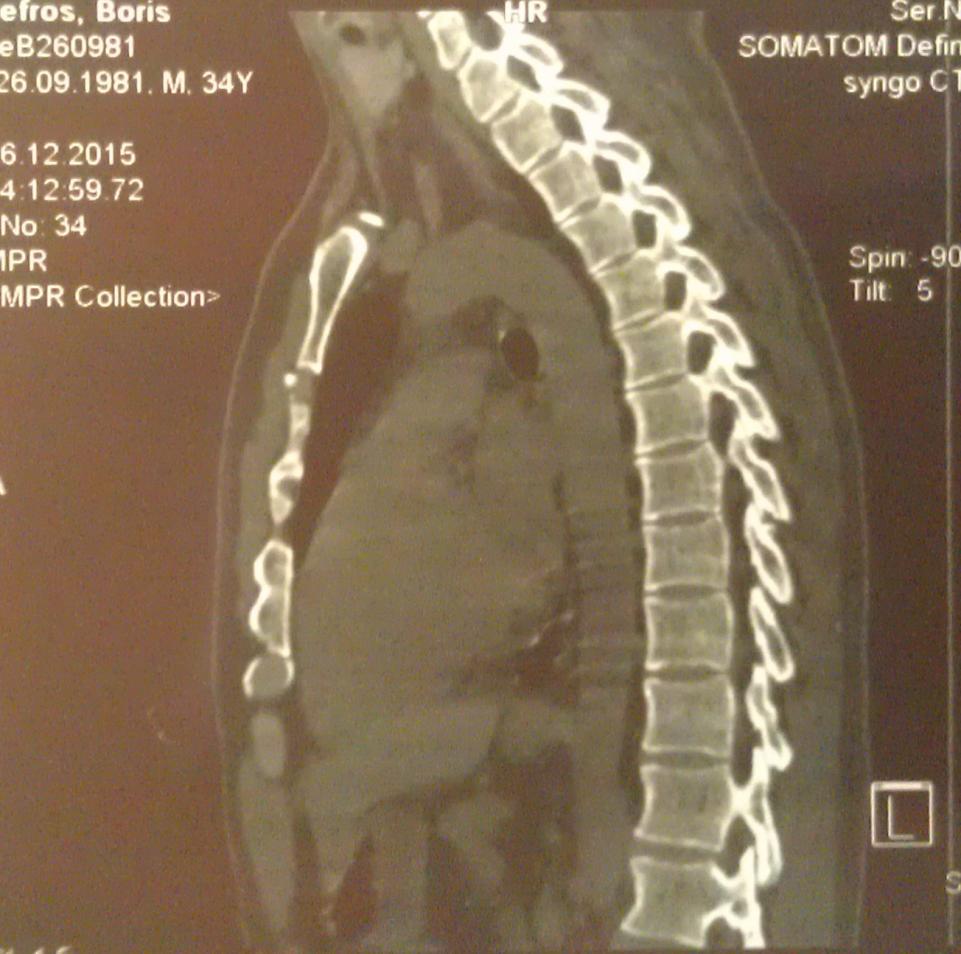

А достаточно ли плохих ревмопроб и компьютерной томограммы, где виден кифоз - чтобы поставить диагноз "болезнь Бехтерева"?

Вот моя компьютерная томограмма позвоночника.

Нажмите на изображение для увеличения

Название: 1 - компьютерная томограмма позвоночник, грудной отдел.jpg

Просмотров: 1600

Размер:	83.2 Кб

ID:	1182Нажмите на изображение для увеличения

Название: 3 - компьютерная томограмма на болезнь Бехтерева.jpg

Просмотров: 1596

Размер:	92.7 Кб

ID:	1184Нажмите на изображение для увеличения

Название: 4 - Снимок позвоночника.jpg

Просмотров: 1571

Размер:	85.8 Кб

ID:	1185Нажмите на изображение для увеличения

Название: 5 - позвоночник при остеохондрозе.jpg

Просмотров: 1628

Размер:	91.0 Кб

ID:	1186Нажмите на изображение для увеличения

Название: 2 - компьютерная томограмма позвоночник.jpg

Просмотров: 1610

Размер:	95.5 Кб

ID:	1183

Судя по снимкам ярко выраженный кифоз, отсюда и сдавливание легких Плохо видно, вроде срастания позвонков нет и это очень хорошо, На данном этапе желательно следить за своим прямохождением-прямосидением и упражнениями способствующими этому.Не ходить к костоломам, ну вроде как потянем-растянем-подстукнем и тд.